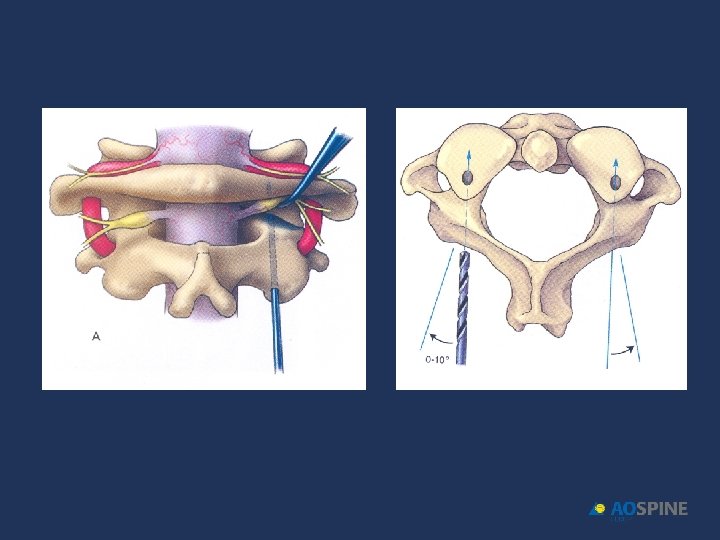

ODONTOID FRACTURES transarticular screws Anterior, Lateral, POSTERIOR (Magerl) 90 -99 % FUSION VERTEBRAL ARTERY LESION RISK 3. 7 - 8. 2% CONTRAINDICATIONS • ANATOMICAL VARIATIONSSCREW TRAYECTORY • GREAT HIGH THORACIC KYPHOSIS • SEVERE OSTEOPOROSIS NEEDS PREOP CT C 0 -C 3 (20% VA ANATOMICAL VARIATIONS))